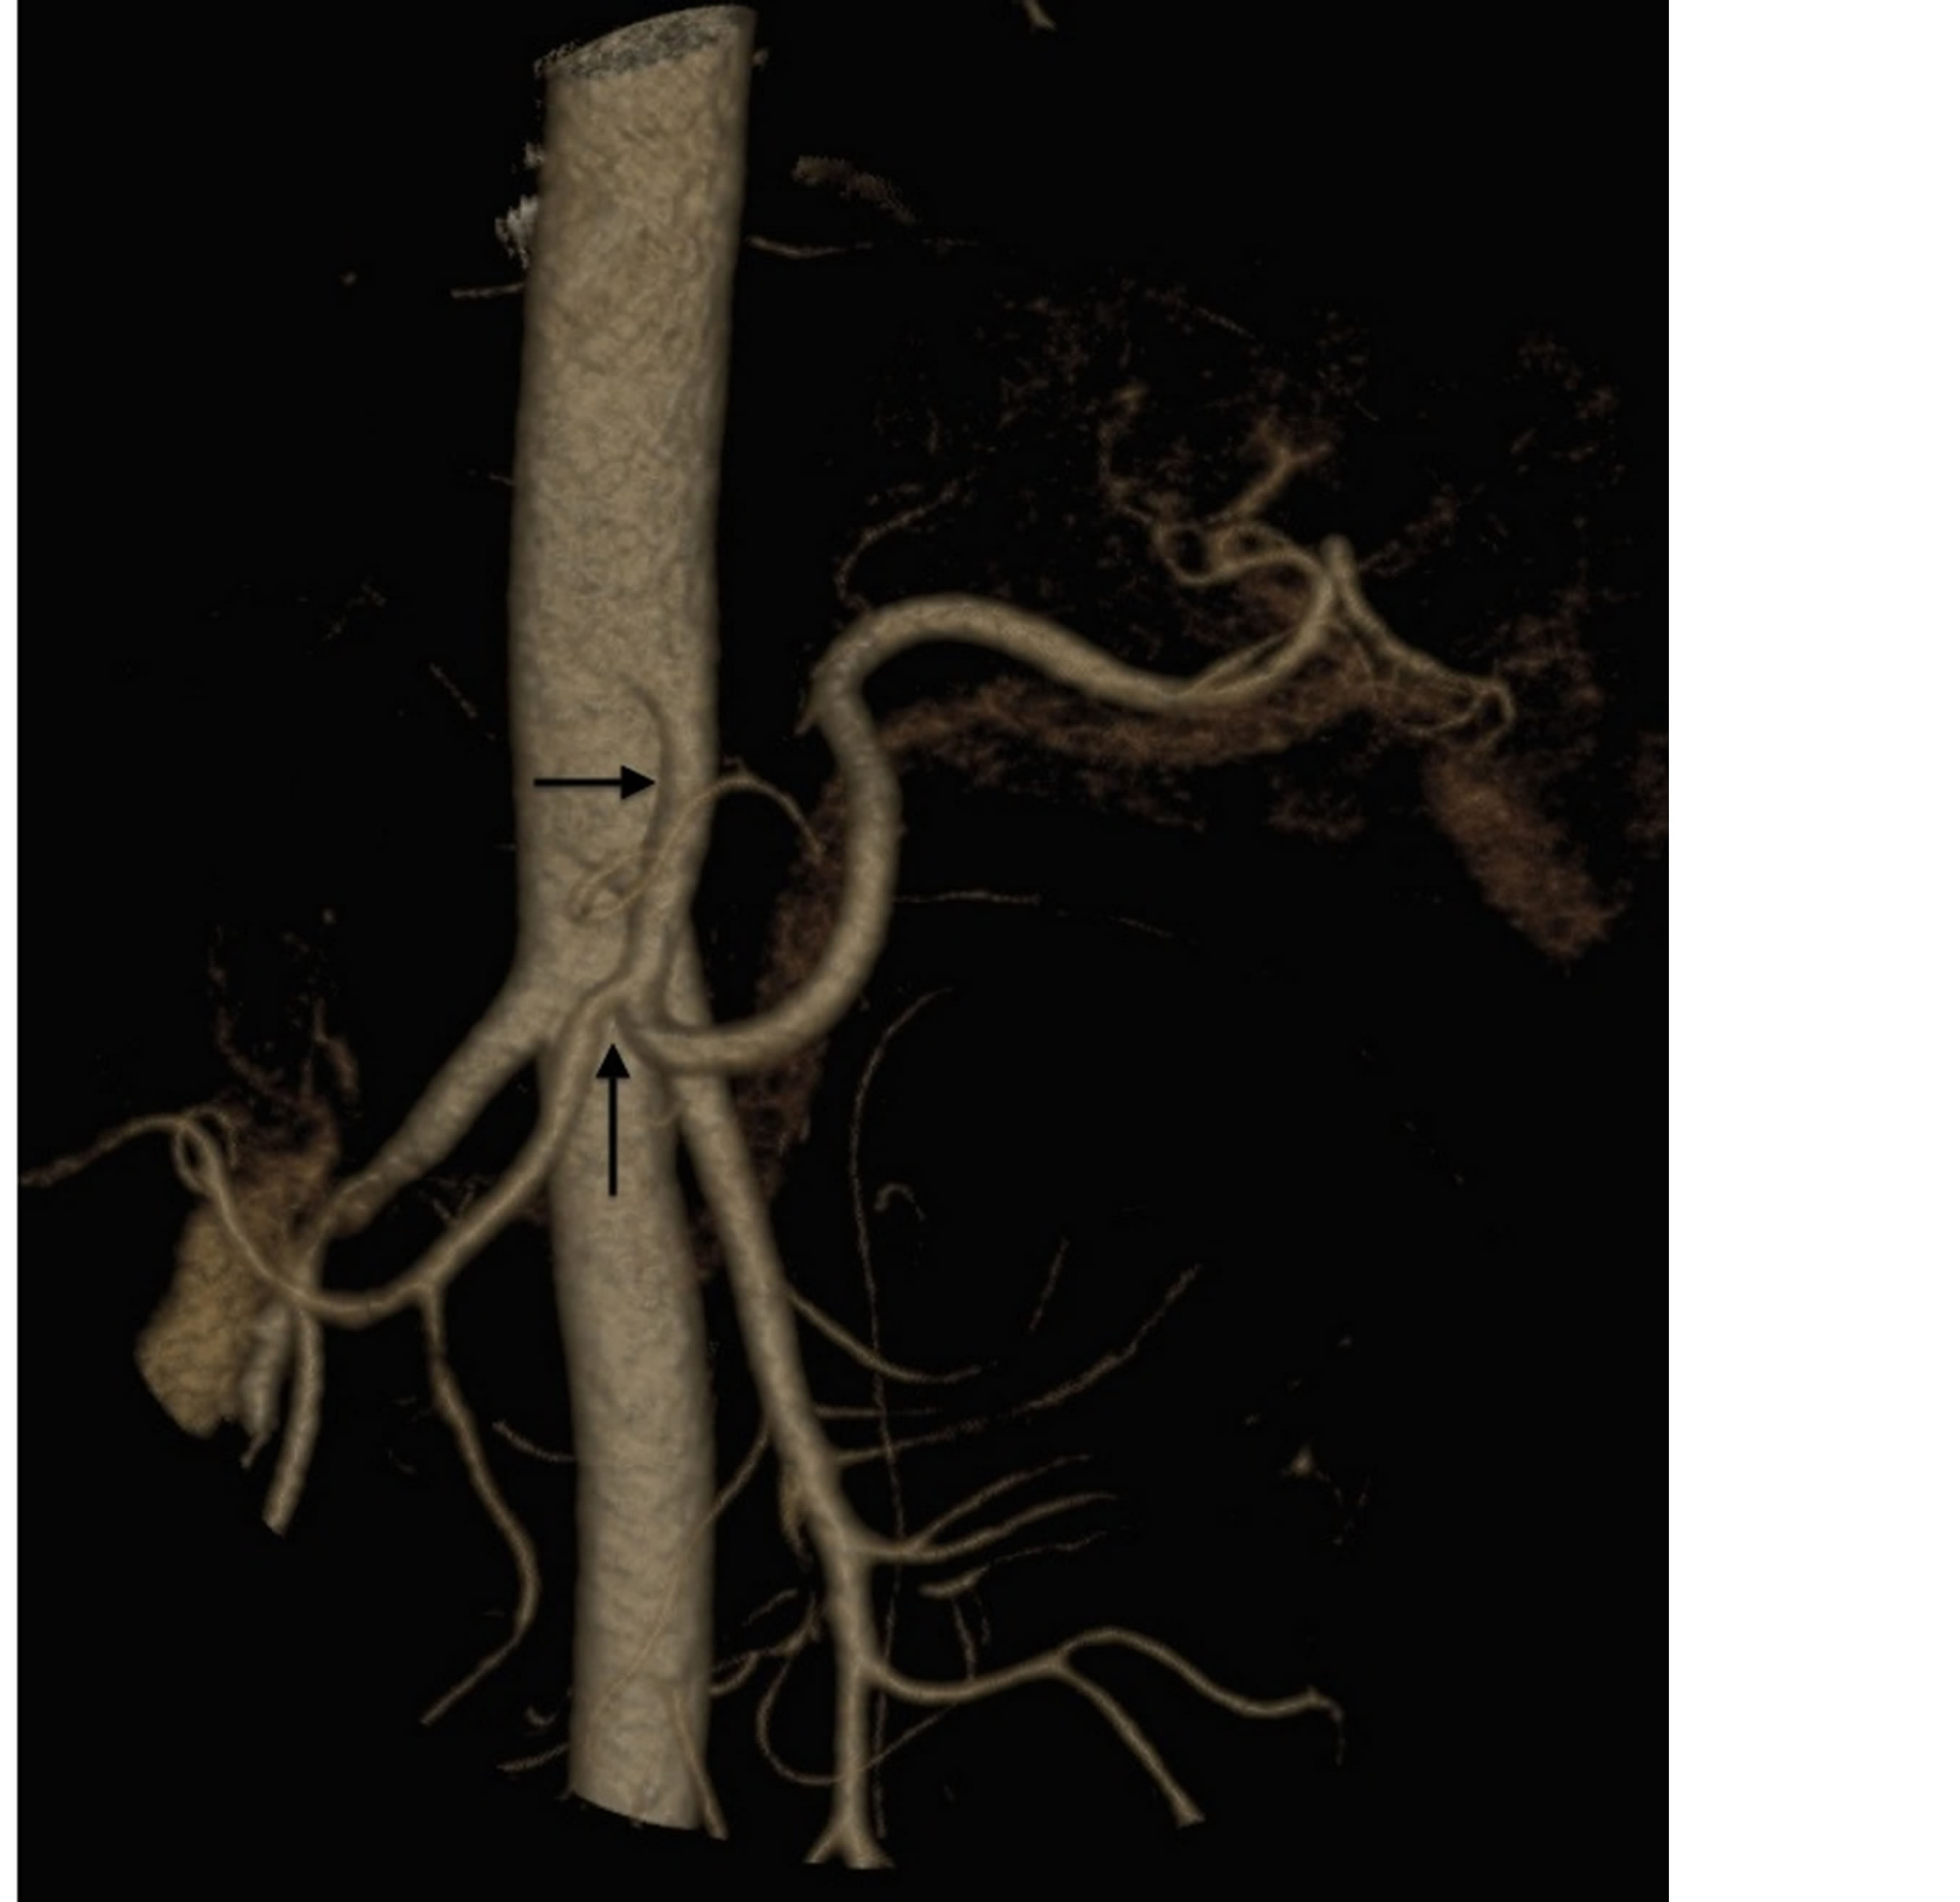

days after the onset of symptoms. Three weeks post nephrectomy abdominal pain recurred caused by a right renal infarct. This was small without any impact on renal function or blood pressure and for these reasons intervention was not attempted. She was treated with oral anticoagulants. The patient continued to have episodes of abdominal pain treated with analgesics, suspected as representing abdominal angina. A year later the patient was placed on a Bosentan regimen and she states that her symptoms have since improved and her blood pressure is no longer elevated. Cardiac studies performed on the patient revealed no abnormalities. Five months after her bosentem was initiated repeat angiographic studies showed resolution of remaining arterial sequelae (Figures 6 and 7) and the return of well being in the patient except for the occasional occurrence of minor episodes of abdominal pain.

Figure 7. 3D CT. Horizontal arrow showing disappearance of the stenosis and pseudoaneurysm of the celiac trunk and vertical arrow showing minimal stenosis of the hepatic artery.

The histological and angiographic findings and clinical symptoms in the current case are a classic representation of reparative phase SAM converted to FMD. An assortment of arterial lesions detected both histologically and radiologically is an important diagnostic feature of both injurious and reparative phase SAM. This variety is created by the varying intensities of the two different arterial injurious lesions, their asynchronous maturation, degree and sites of florid repair and segmental distribution [3]. This case illustrates the varying types of lesions typifying reparative phase SAM. These are medial-adventitial tears repaired by granulation tissue that serves as both sites and sources of dissecting and mural hematomas (Figures 8-10). Prior studies of SAM have shown that these lesions are initiated from hemorrhage in the granulation tissue filling the adventitial-medial separation plane rather than from intimal tears [1,3] and as this case illustrates, by the unsatisfactory stent attempt, this bleeding can be traumatically induced. We suspect that the cuff surrounding the celiac axis (Figure 1) represents a mural hematoma possibly partially or totally filled with granulation tissue. The second lesion is sequela aneurysms that are well repaired by granulation tissue that forms plaques over adjacent intact arterial intima and may bedeck surviving medial islands (Figure 8). These frequently grossly appear as large fusiform aneurysms (Figure 2) formed by two or more adjacent microscopic aneurysms created by the segmental distribution of SAM’s gaps. The latter fashions the saw-toothed appearance frequently found in medial FMD. The third lesion is the occurrence of medial granulation tissue with fibrosis repairing areas of mediolysis Figures 9 and 11). This change always commences in the outer media and may extend inwardly to involve some or all of the inner media. It is often patchy because of the survival of muscle cells in zones of mediolysis. Arterial stenosis, the forth lesion, is cause by the aforementioned lesions and reparative intimal plaques (Figures 3, 5 and 11). The fifth lesion is the formation of thrombi formed in both the aneurysms and pseudo-lumens of dissecting hematomas with thrombo-embolization developing distal to these lesions.

The renal vein fibrotic lesion, consistent with the repair of an endothelin-1 (ET-1) induced venous angiopathy, suggests ET-1 may have potentiated the pressor activity of norepinephrine [1,4]. This lesion frequently accompanies abdominal SAM. ET-1, synthesized in capillaries in the adventitia of the adjacent abdominal arteries, cross-talking with the norepinephrine produced in the ganglia of the efferent sympathetic nerve endings in the outer arterial wall potentially can convert a norepinephrine induced vasoconstrictor physiological stimulus into SAM [1]. However, the role played by ET-1 in SAM is still uncertain. The possibility that it may be additionally released in response to the formed sequelae was the rational for treatment in this patient with the ET-1 antagonist bosentem. The disappearance of all the remaining angiographic sequelae following 5 months of treatment with this agent supports this notion. However, this needs confirmation since spontaneous resolution of sequela aneurysms is reported in SAM [3]. Finally, the pressor effects of norepinephrine may be further intensified because of the increased sensitivity of the alpha-1 adrenergic receptors to adrenaline and by inference to the agonists causing SAM reported in premenopausal females [14]. This finding possibly accounts for the female gender preference in FMD.